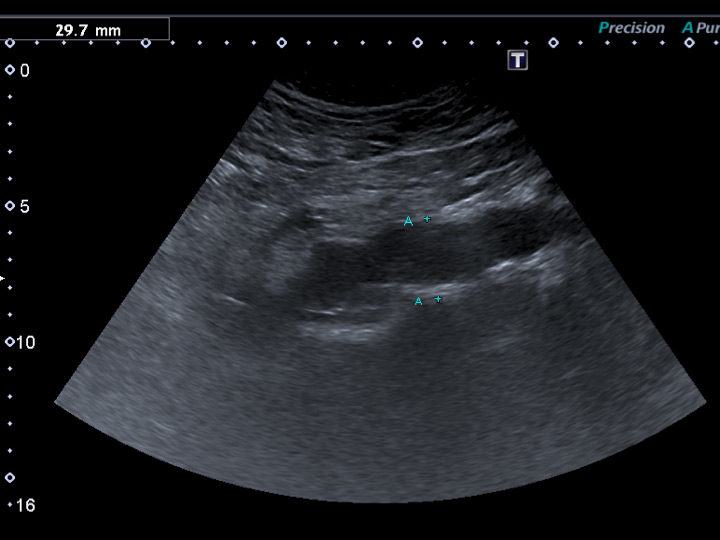

Figure 1

Previously undiagnosed small abdominal aortic aneurysm detected on vascular duplex ultrasound in a 62-year-old smoker with erectile dysfunction, otherwise asymptomatic regarding cardiovascular disease.

Figure 1 shows a sonographic depiction of a previously undiagnosed abdominal aortic aneurysm in an otherwise healthy and asymptomatic smoker referred for vascular workup of erectile dysfunction.